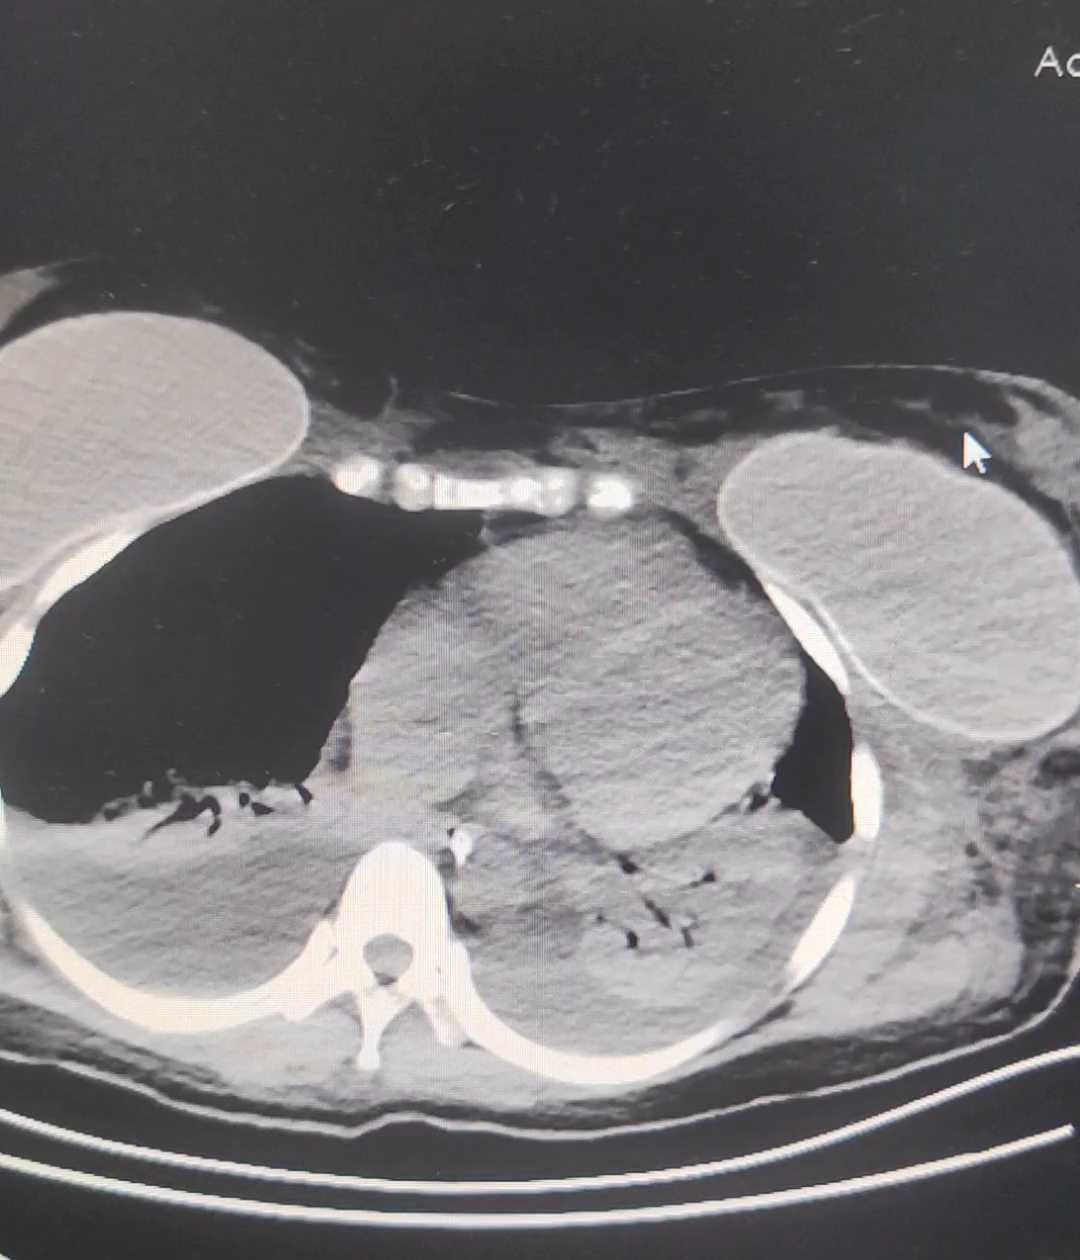

继续予患者护胃,补液,纠正电解质。去甲肾上腺素升压!之后患者胸闷,憋死加重,予患者完善bnp,回示:3463,予患者进一步补钙,呋塞米利尿,乳果糖导泻!就这样患者持续未见还好转,收入icu。在icu予患者气管插管,继续胃,强心,利尿,改善循环,血滤加灌酒等对症治疗,患者血压仍低,与患者晚上腹部CT。如下:

肠梗阻,胃内大量药片,最终用胃镜取除除了胃内容物!